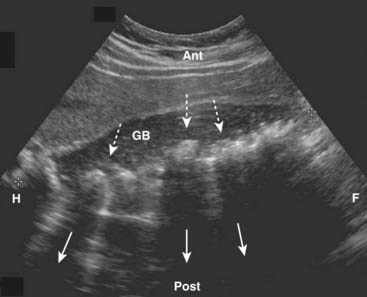

Figure 19-1 Normal gallbladder, sagittal view.

The gallbladder (GB) is normally filled with bile and is sonolucent. The wall of the gallbladder is less than 3 mm in size and slightly echogenic (solid white arrow). By convention on a sagittal view, the patient’s head is to your left (H), feet to your right (F), anterior is up (Ant), and posterior is down (Post).